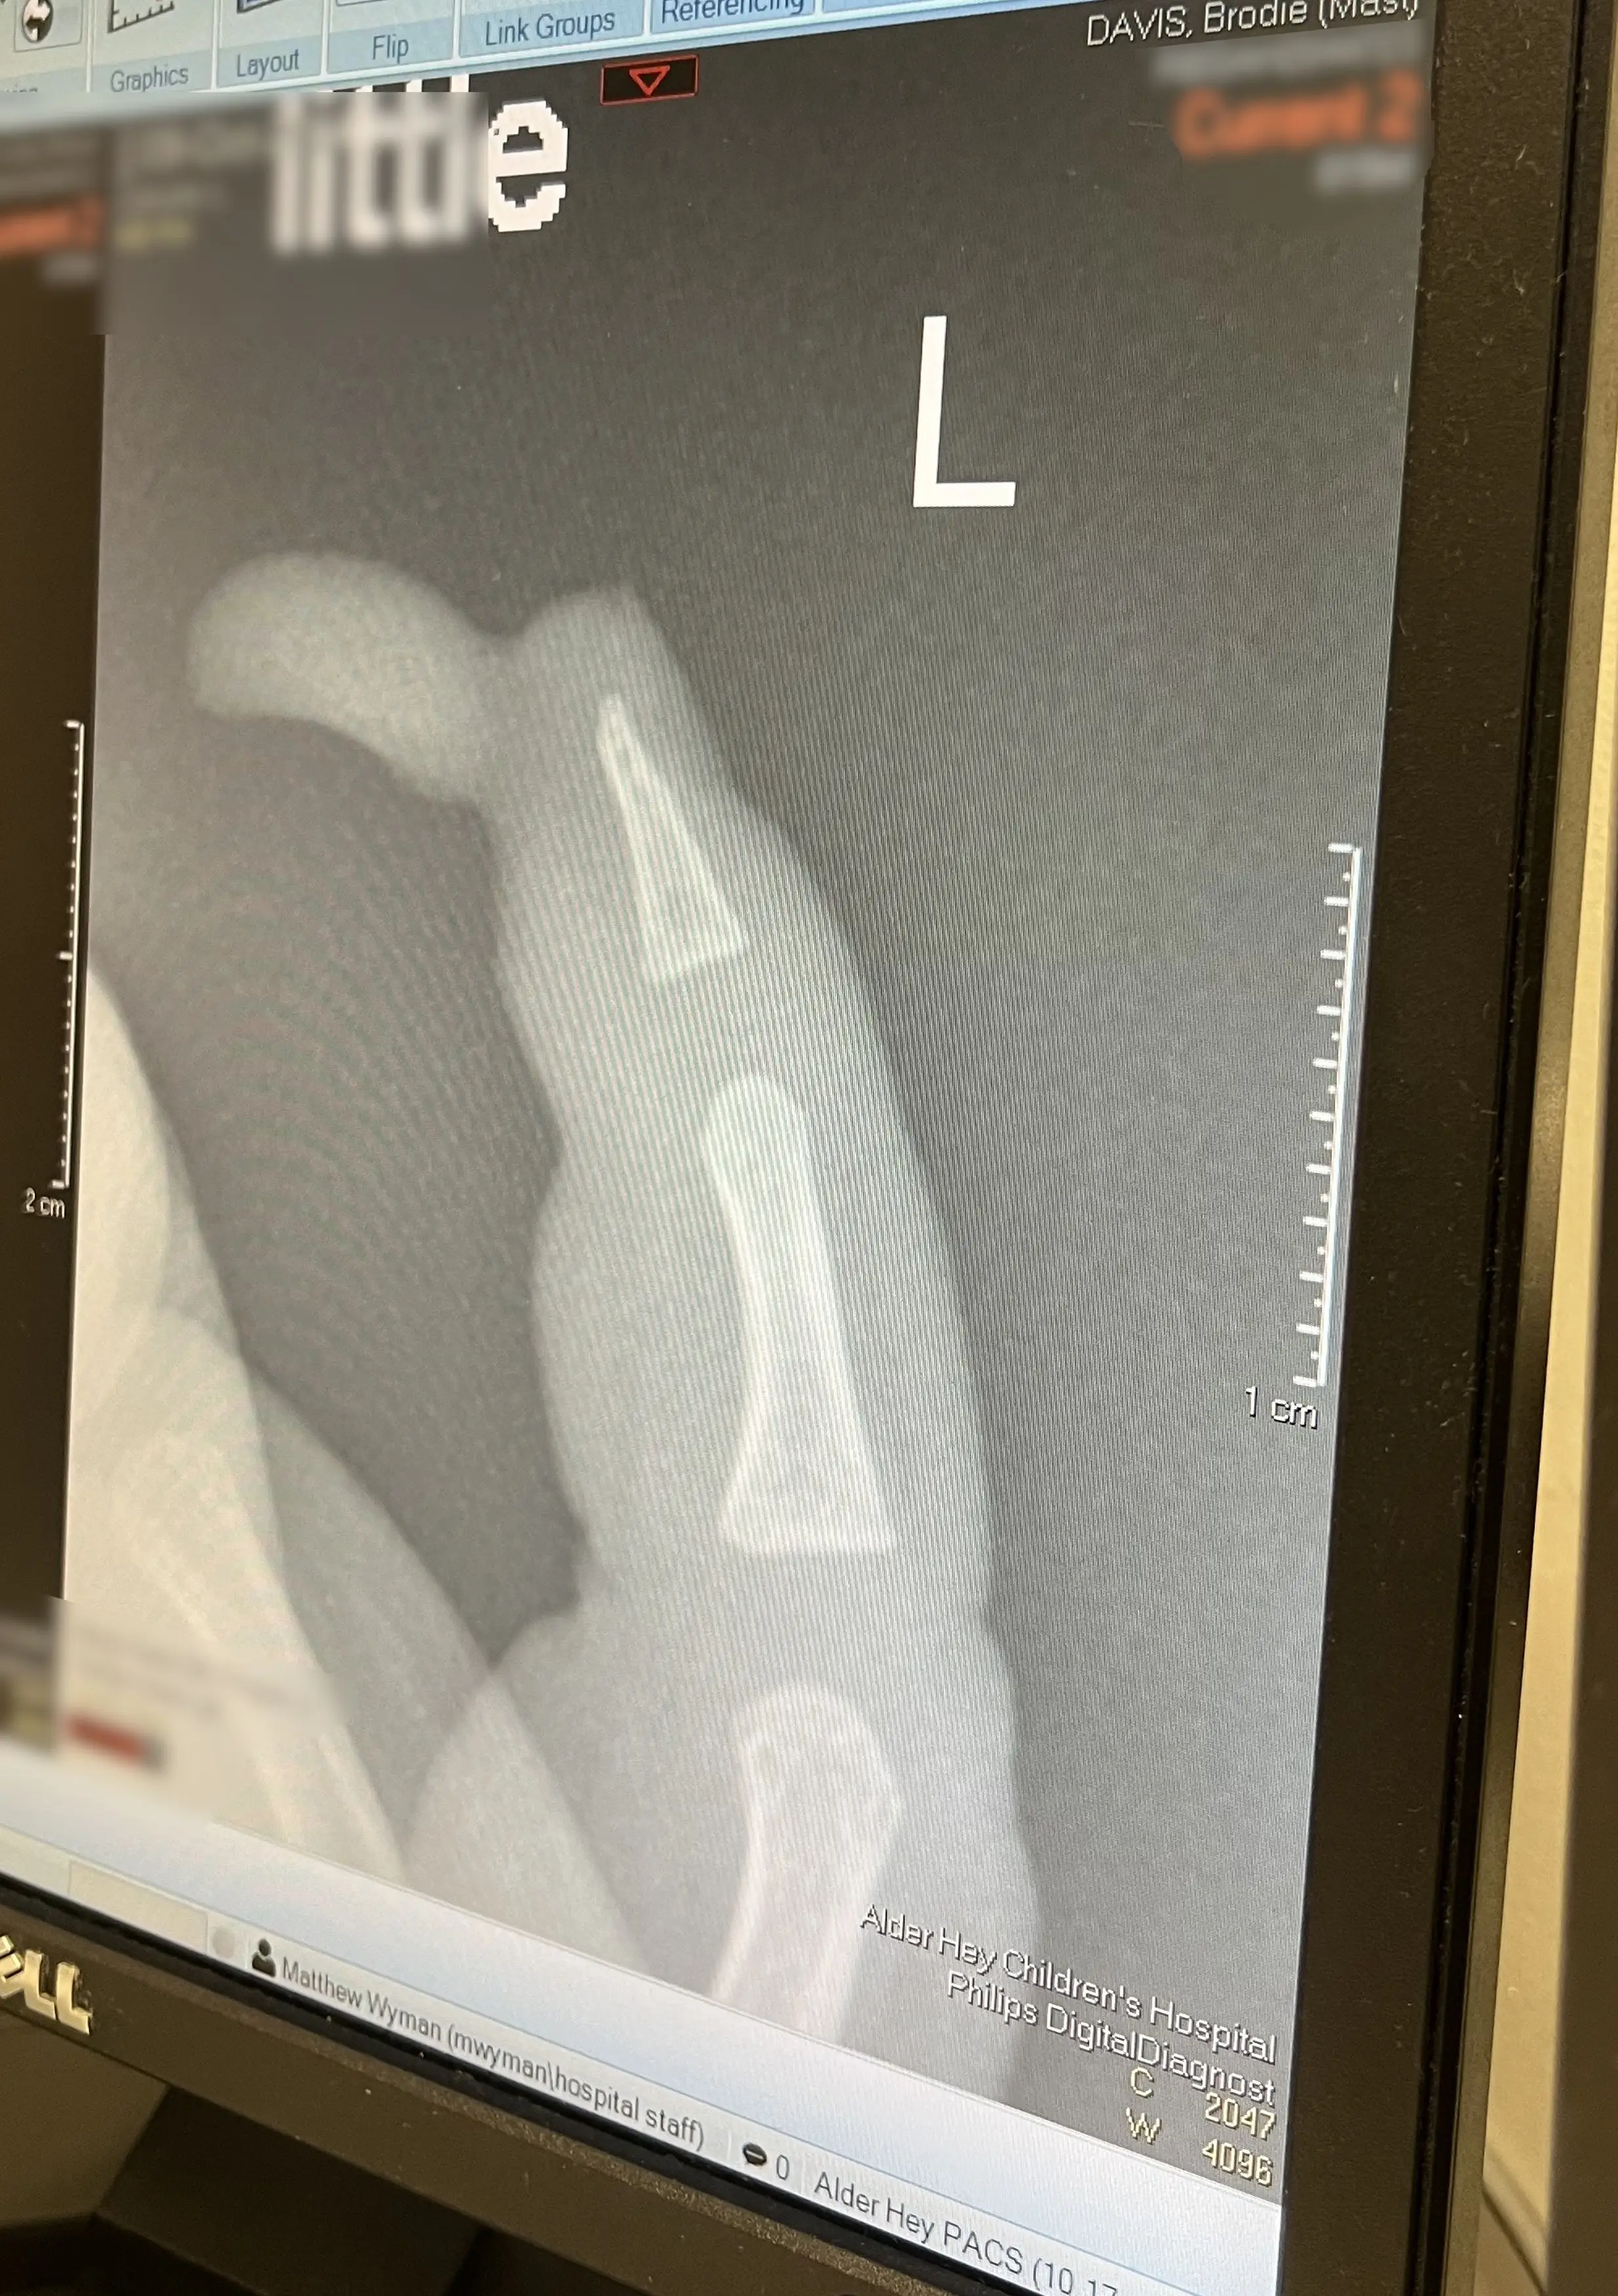

Liverpool woman Amie, 29, said she almost passed out when she was her son's finger was 'hanging on by a thread' after the accident and rushed him to Alder Hey Hospital.

The one-year-old went in for an operation to reattach the tip of his finger and may need a skin graft in the future.